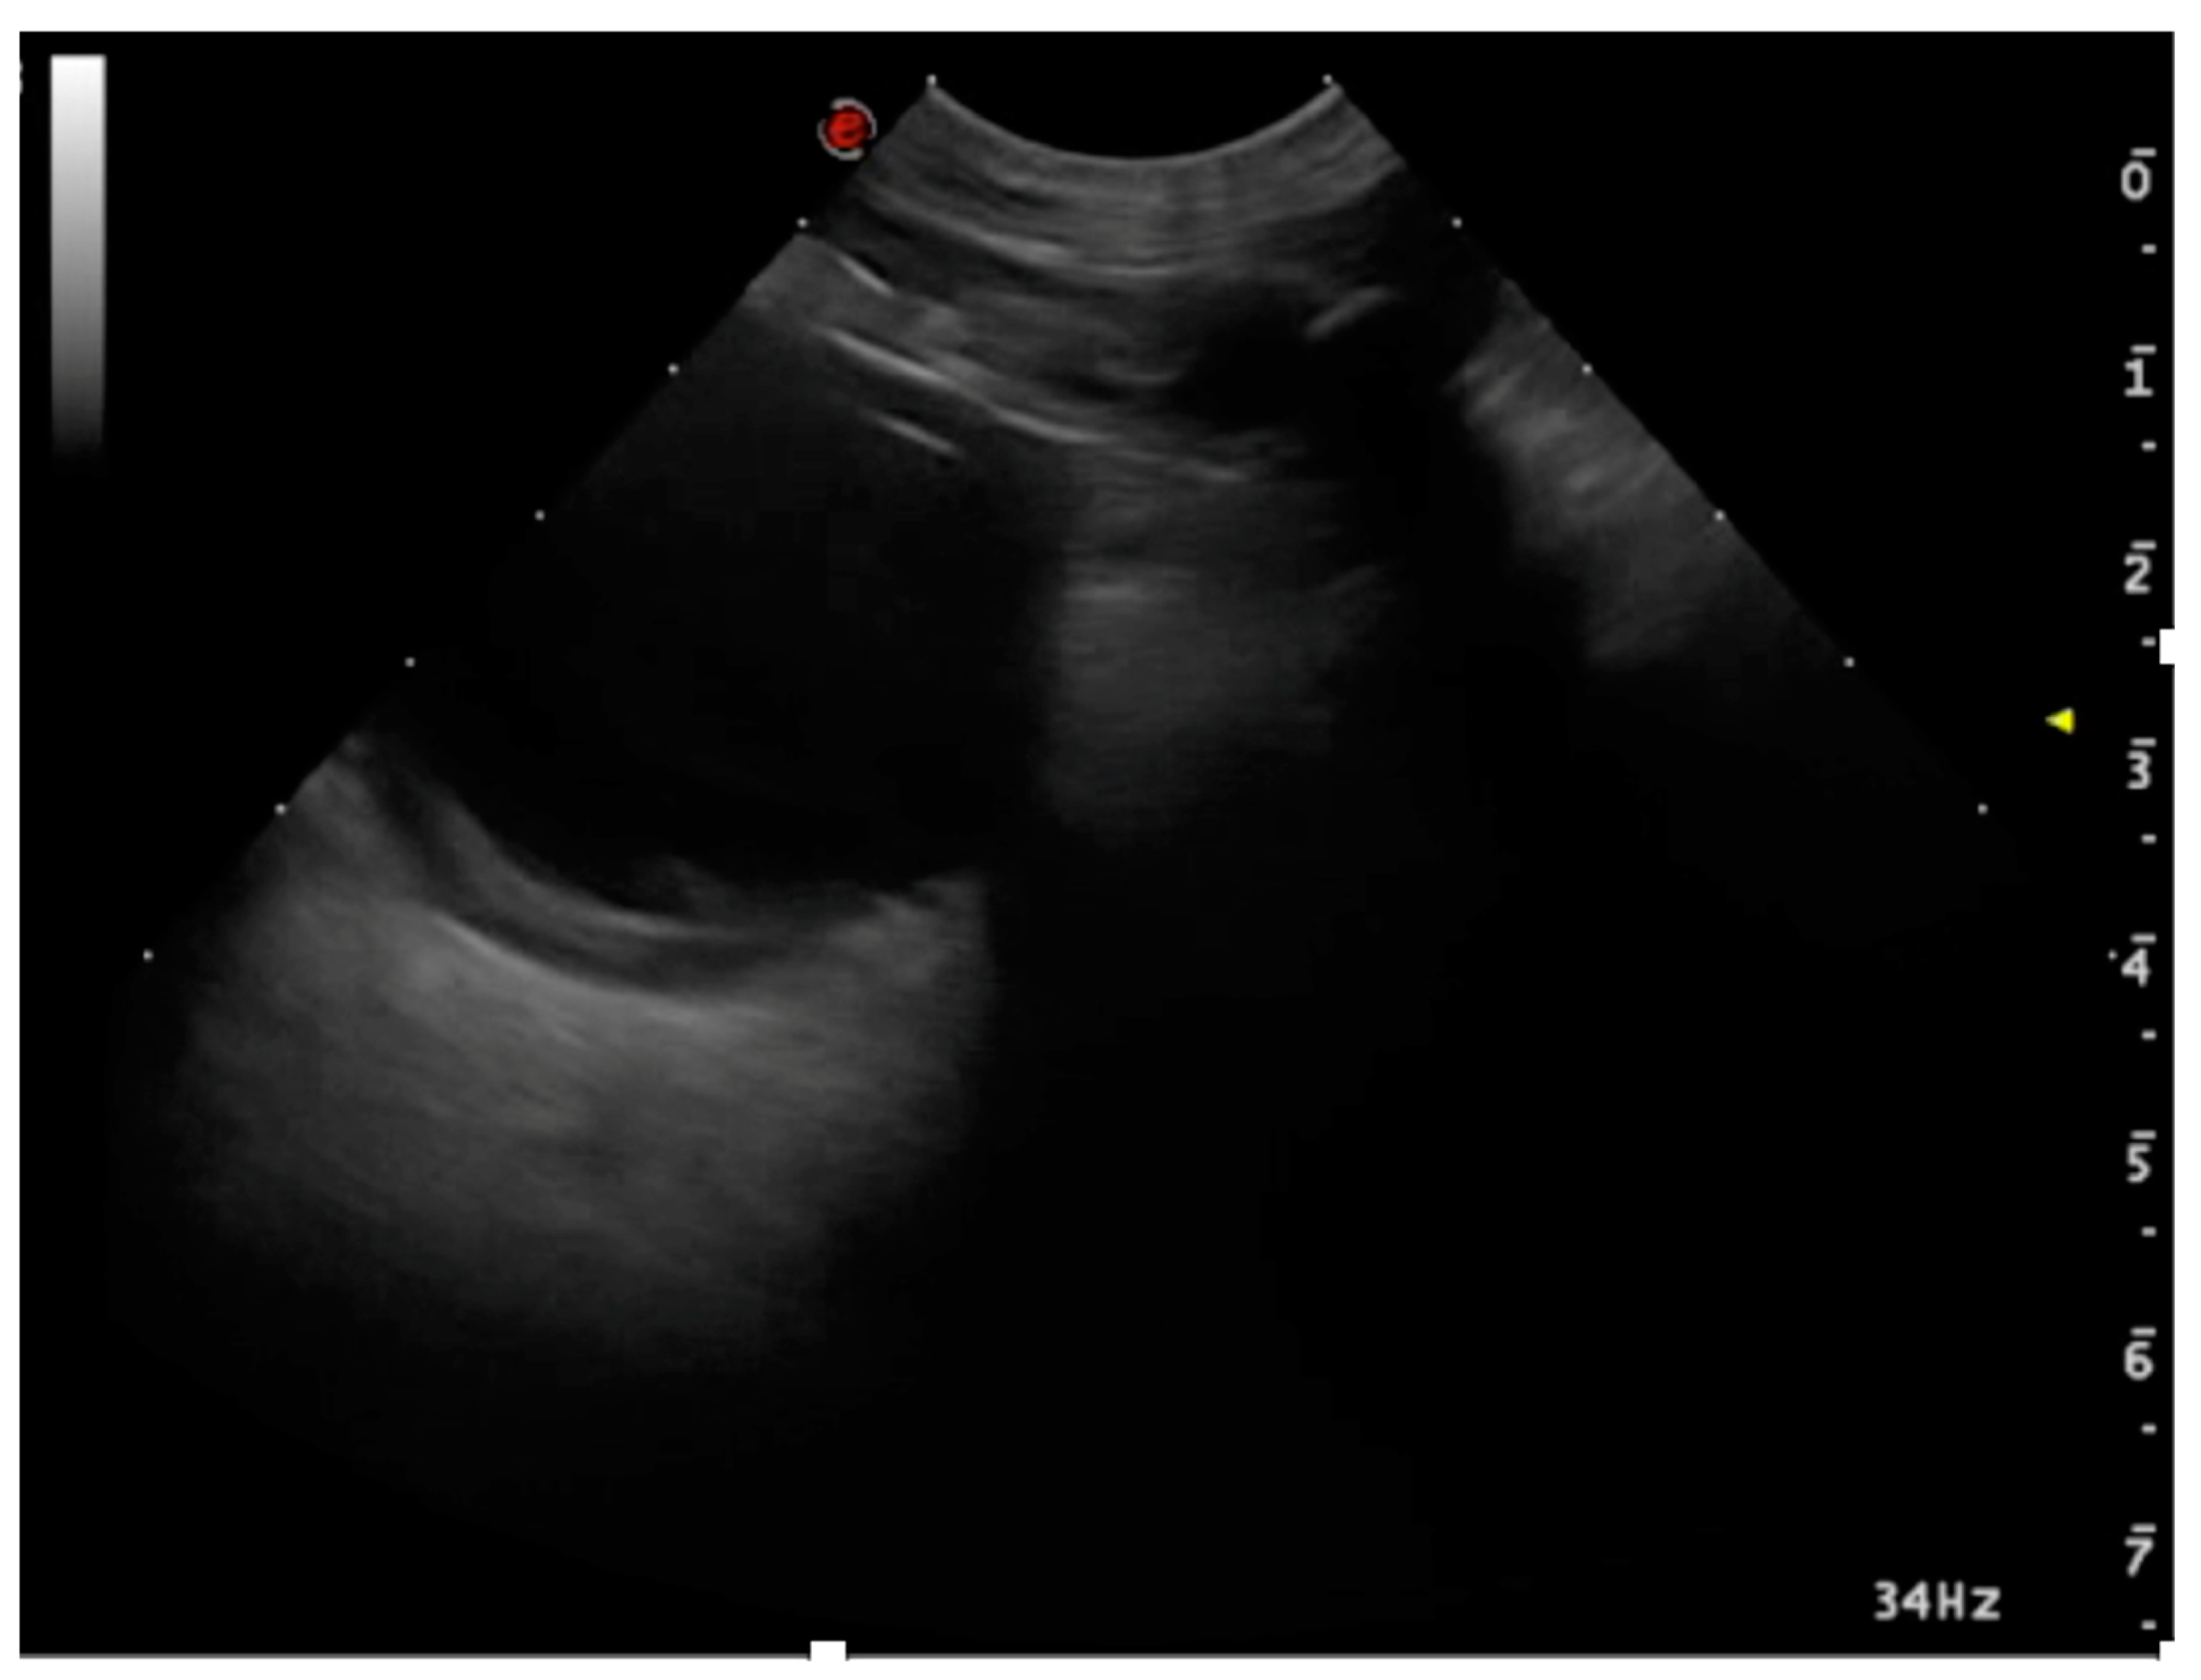

3.1.2. Pleural Effusion